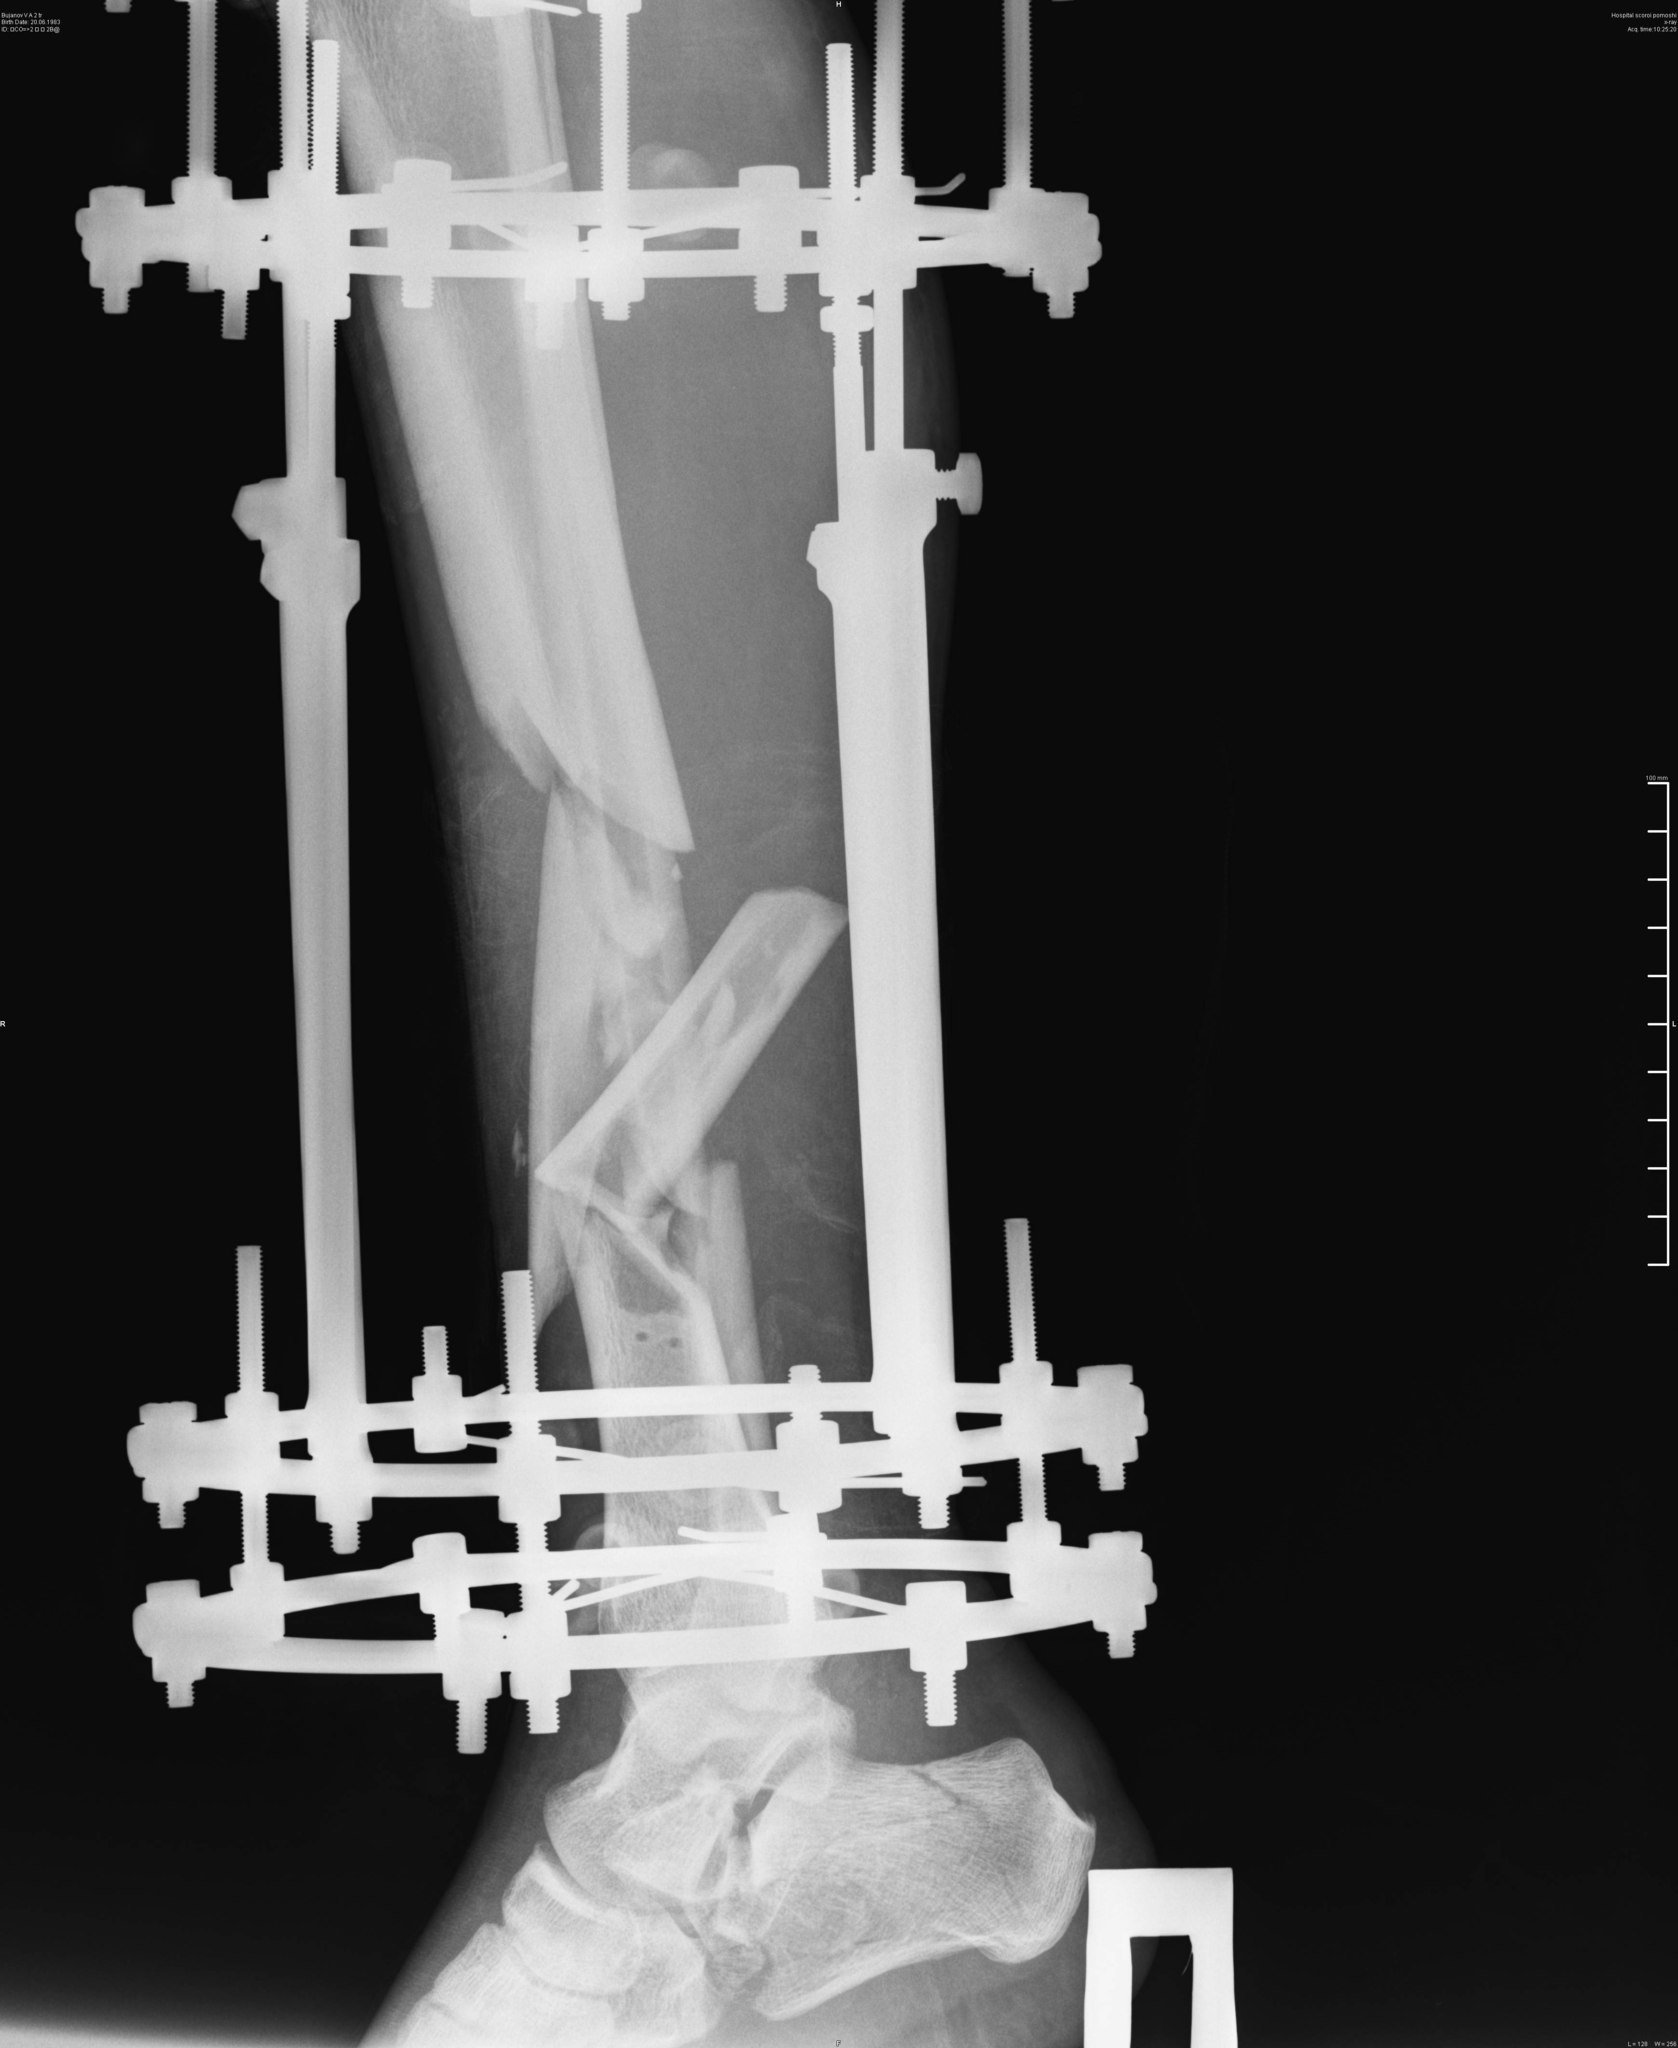

Эпикриз: Сочетанная травма. ЗЧМТ. Сотрясение головного мозга. Открытый многооскольчатый перелом обеих костей с/3 правой голени со смещением отломков. Открытый многооскольчатый перелом пяточной, ладьевидной, кубовидной кости, подвывих пяточной кости. Обширные рваные раны области правой стопы, правой голени.

было это еще 7 июня, но до сих пор, по прошествии двух операций ему не собрали все кости. Оказалосьь, что одну кость забыли на месте ДТП и теперь вместо нее требуется имплант. На одной ноге у него сейчас 18 переломов и 3 из них гниют, один из кусков кости встал поперёк, врачи опасаются её доставать или разворачивать, ибо можно занести ещё больше инфекции, если делать, то надо делать сразу всё комплексно, а пока приходится постоянно чистить, чтоб не было заражения, никакие обезболивающие уже не помогают, организм уже к ним адаптировался, и приходится терпеть эти боли. Нам же остается только медленно собирать деньги.